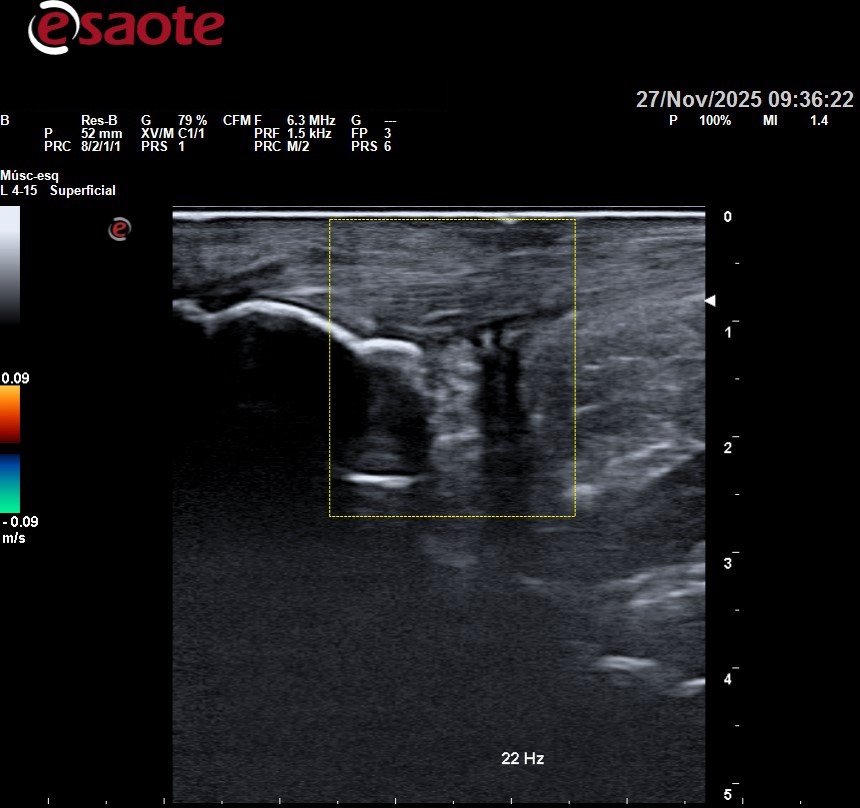

“La ecografía permite estudiar los tejidos por debajo de la piel con precisión milimétrica sin abrirla con el bisturí, valorando si hay lesión en los mismos o no, para centralizar adecuadamente el tratamiento”.

- La ecografía permite visualizar en tiempo real la estructura interna del pie, incluyendo huesos, músculos, ligamentos, tendones y tejidos blandos. Esto facilita la identificación precisa de patologías como fascitis plantar, tendinitis, neuromas, quistes, entre otras.

- A diferencia de otras técnicas de imagen, la ecografía permite evaluar las estructuras del pie en movimiento, lo que es crucial para entender cómo ciertos problemas pueden verse afectados por la biomecánica del pie y la marcha del paciente.

- La ecografía puede utilizarse para guiar procedimientos terapéuticos como inyecciones de corticoides, aspiración de quistes o hematomas, y otras intervenciones mínimamente invasivas. Esto aumenta la precisión y eficacia del tratamiento.